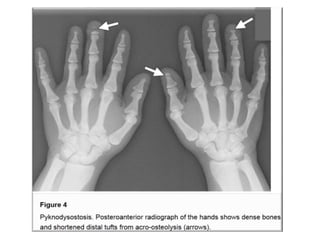

• Dwarfism

• Pectus excavatum

• short fingers from acro-osteolysis

• hypoplasia of the facial bones, causing dysmorphic facial

features.

• Radiographically, there is generalized osteosclerosis similar

to osteopetrosis, but with preservation of the medullary

canal of long bones.

• Dense vertebral bodies with characteristic

sparing of the transverse processes is seen.

• Because the medullary cavities are preserved, patients

with pyknodysostosis (unlike patients with

osteopetrosis) tend not to have concurrent anemia.

• On the other hand, as with osteopetrosis, the bones

are brittle and prone to recurrent fractures.